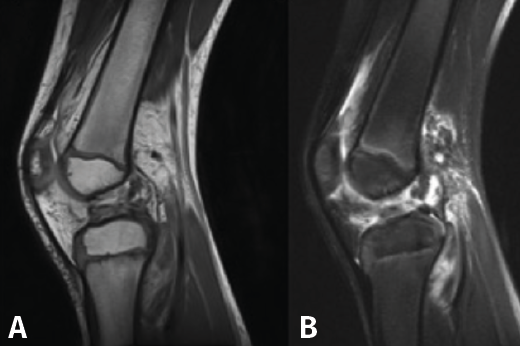

La resonancia magnética es el método de elección para el diagnóstico, con una sensibilidad del 95% y una especificad del 88% para las lesiones del LCA en la edad pediátrica(59). También mostrará, con alto grado de fiabilidad, la presencia de lesiones concomitantes, meniscales y condrales(60)(Figura 2).

Figura 2. Resonancia magnética de rodilla (A: T1/B: T2) de un paciente de 6 años con rotura completa del ligamento cruzado anterior.